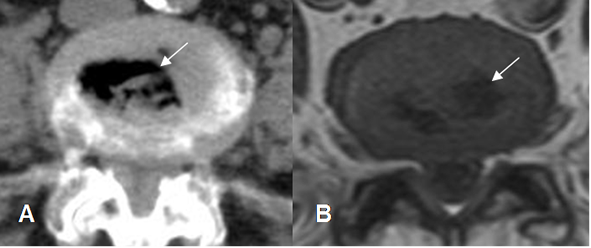

Fig 35. Fenómeno del vacío.

A: TAC axial y B: RM axial en T1. Presencia de aire dentro de los discos, por proceso degenerativo.